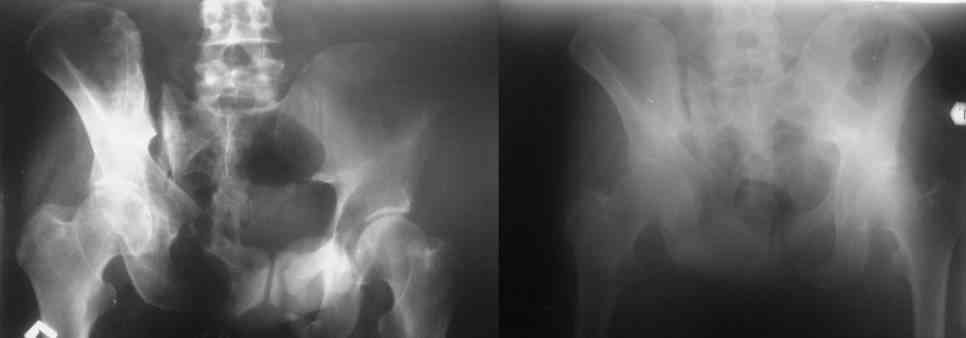

Здравствуйте, уважаемые коллеги. Ситуация такая. Мужчина 50 лет, невысокий, худой. Перелом костей таза пять месяцев назад. Пришел на костылях. В поисках адекватной помощи в краевых больницах был "переадресован" не ближе чем как в Курган и Москву. Денех естессно нет + семейные неурядицы в связи с приобретением статуса инвалида. Ехать, после хождений по мукам, теперь никуда не хочет. Готов на оперативное лечение в нашем отделении.Больной стабильный. Неврологического дефицита нет. Функции тазовых органов в норме.

Остается только вариант закрытого аппаратного лечения. В аттаче положение отломков на вытяжении в прямой (АР) проекции. Для сравнения снимок до и во время вытяжения.

Первоочередно для тазовых операций важно обследование, снимки таза в инлет, оутлет и прямая

проекция.

На сравнительном снимке правый полутаз опустился

недостаточно, можно добавить вес и сделать все стандартные снимки.